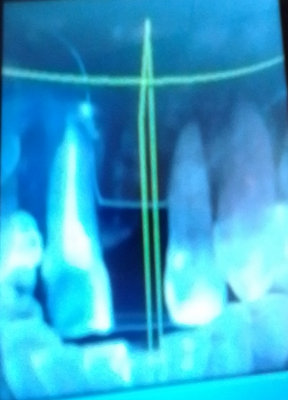

2 месяца назад сделали резекцию передних двух зубов. Кисты были достаточно очень большие. Операция и послеоперационный период прошли нормально, но примерно где-то через месяц начались снова боли сначала в десне, а потом и начали болеть зубы.

Врач прописал мильгамму, траумель и новопасит, сказал, что будет лучше, в итоге ничего не улучшилось, стали реагировать на холод (на питание и на улице от воздуха). Сейчас же болят и при накусывании.

О каком восстановлении речь. Конечно нет, скорее всего имеет место рецидив, отсюда и Ваши беспокойства.

Чтобы понять причину сделайте сегментное К/Т и все увидите.